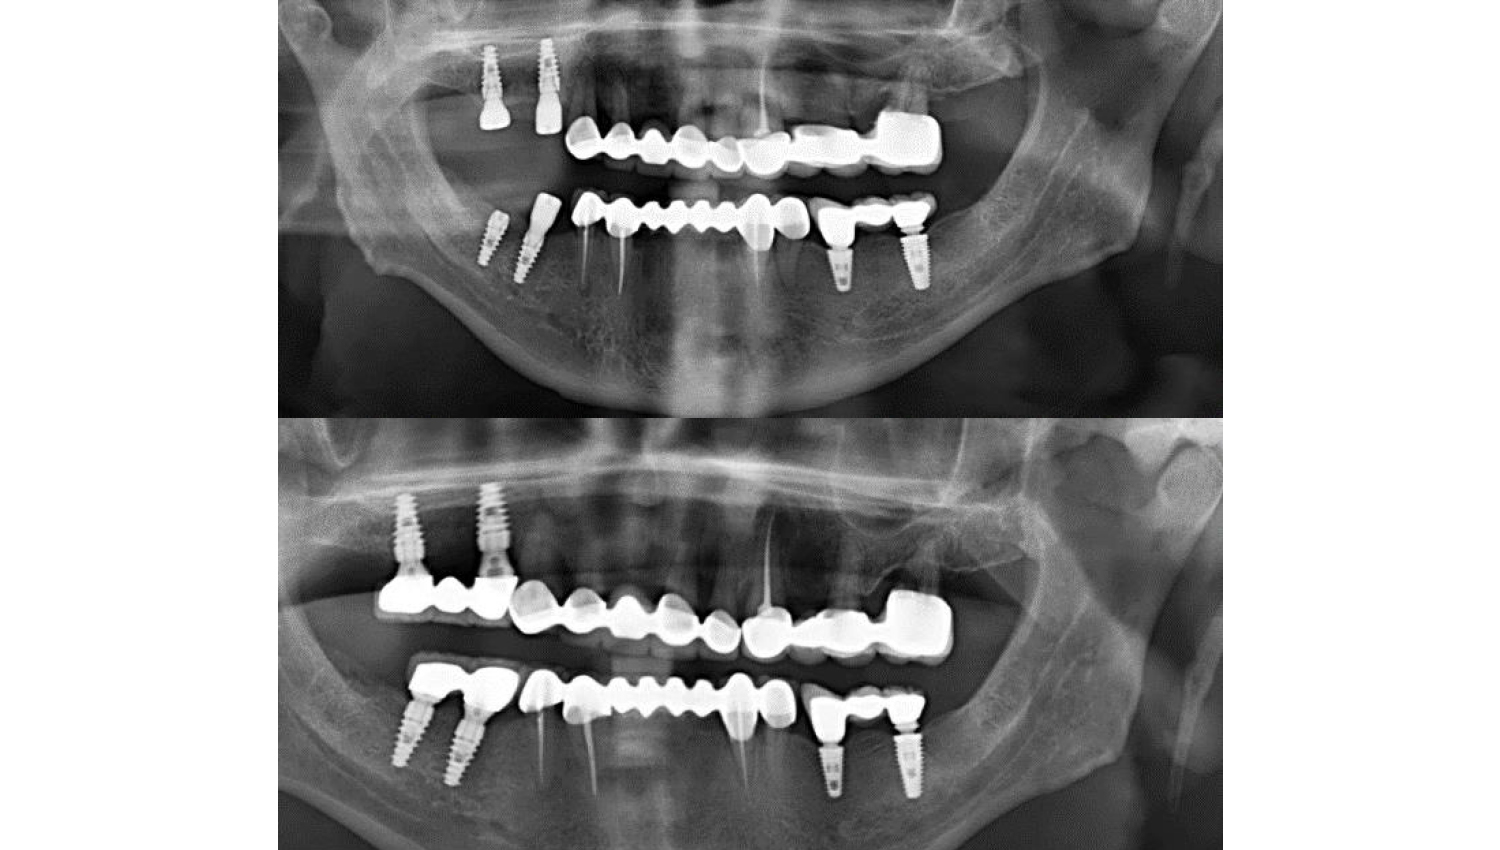

2.Osstel measurements were taken from our patient.

3After Osstel measurements, implantation was performed with Powerbone Dental Implant. Radiological imaging after implantation is shown below.